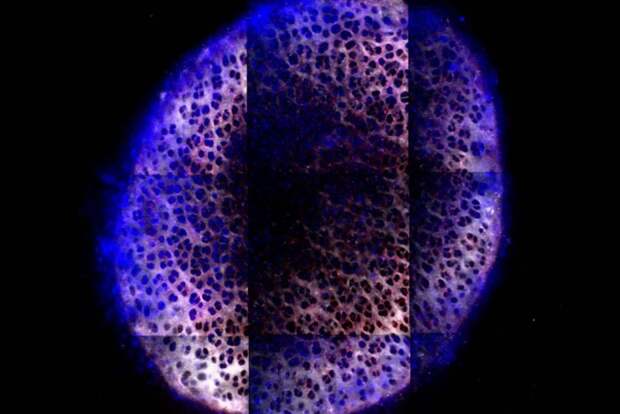

The sphere-shaped molecule they came up with contains many branched structures called dendrimers that branch from a central core. The molecule has a…